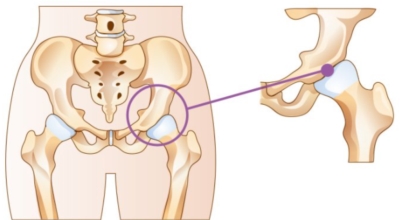

고관절이란 골반을 지탱하는 관절로서 근육과 힘줄로 구성되어 있어요. 학계에서는 고관절을 엉덩이 관절이라고 부르기도 하며 인체의 하중을 지탱하는 아주 중요한 관절입니다. 각별히 고관절은 우리가 정상적으로 서있거나 움직일 수 있게 만들어주며 달리기, 점프, 무거운 무게를 들 때 최대 체중의 2~10배 가량의 하중을 받기 때문에 적절한 관리가 필요합니다. 오늘은 고관절에서 일어날 수 있는 고관절 통증 증상에 관해서 알려드리도록 하겠습니다.